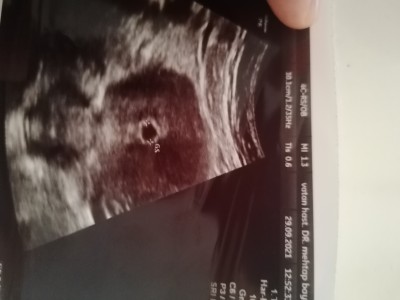

Merhaba.  Son adet tarihim 2 Ağustos. Gebelik 9. Hafta olarak gözüküyor. Ancak doktora gittiğimde haftama göre ortada bebek yok kese var. Boş gebelik dedi doktor ve bu hafta aldırmam gerektiğini söyledi. Kafamı karıştıran ise şu kızlar. Ben düzensiz adet olan biriyim 35 ila 36 gün de bir adet oluyorum ve eylülün 8 inde normalde adet olmam lazımdi ama olmadım sonra ayın 10 unda doktora muayene olmaya gittim alttan ultrasonla baktı ve Rahim kalinlasman var adet veya gebelik için hazırlanıyor olabilir dedi. Bende sonra 14 eylülde idrar testi yaptım ve pozitif çıktı. Sonra doktoruma gittiğim de kan verdim kan değerinde de gebelik var dendi. Bir daha ki hafta gel kesen görelim dedi o da 21 eylülü ve kesem 4.30 mm dedi. Kesenin etrafında biraz kanma var progestan verdi onu kullandım. Daha sonra bir daha ki hafta gene gel kontrol edelim dedi. Doktor izne ayrılmışti ve beni başka bi doktora yönlendirdiler. O da hemen boş gebelik bu dedi. Kalp atışı olmalıydı dedi. Bende durumu izah ettim ama bana kurtaj olman gerekiyor dedi. Ve kese boyutu 7.9 mm di ve bebek görünmüyordu. Simdi benim bebeğim kaç haftalık ya. Kafam allak bullak oldu bebek var mı yok mu iyice bunaldım.

Benimde son adet tarihim sizinle aynı haftamla uyumlu değil bir hafta geri gösteriyor ultrason ama doktor hayır uyumlu dedi anlamadım ama ben ultrasona göre 5 haftalıkken duydum kalp atışını bir hafta sonrada kesinleşti kesenin içinde nokta gibi bişey vardı sizin resimde üzgünüm ama göremedim başka doktora mi gorunseniz